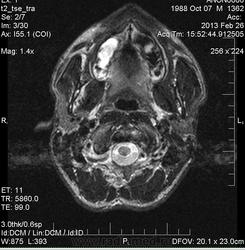

Правосторонний гайморит, фронтит, этмоэдит в фазе выпота. Киста ли это в верхне-медиальных отделах правой в/ч пазухи?

В мае удаляли зуб справа. Беспокоят гнойные выделения из полости носа. На ортопонтограмме со слов пациента без патологии. В области альвеолярного отростка верхней челюсти  справа в области коренных зубов визуализируется зона отека? деструкции?

У товарища похоже, что и фронтит и гайморит справа. Слева утолщенная слизистая. А словам, что на орто норма, можете не верить.

А может быть это аспиргиллема в правой в/ч пазухе?